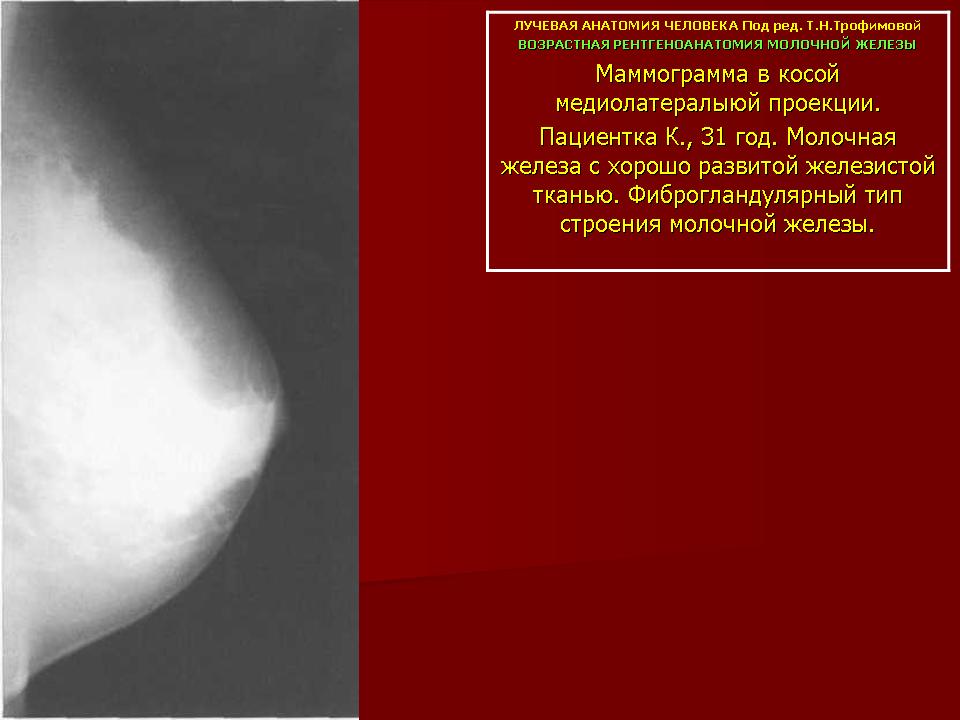

УЗИ молочных желез в Москве

УЗИ молочных желез — информативный и безопасный метод диагностики, с помощью которого можно точно оценить состояние желез, обнаружить доброкачественные и злокачественные образования, уточнить диагноз. Это доступное по цене исследование безвредно и не несет лучевой нагрузки. Оно имеет большое значение в ранней диагностике заболеваний и нередко применяется в профилактических целях. На УЗИ может направить маммолог, онколог, эндокринолог, гинеколог.

При отсутствии жалоб проходить УЗИ необходимо пациенткам возрастом 25–39 лет один раз в два года, старше 40 — ежегодно. УЗИ молочных желез после 40 лет важно проводить регулярно с целью профилактики онкологических заболеваний. Гормональные изменения, связанные с возрастными процессами, повышают риск появления новообразований.

Подготовка и правильное планирование

Исследования молочных желез необходимо проходить в определенные дни менструального цикла. Это объясняется тем, что ткани изменяются в соответствии с изменениями гормонального фона и фазами цикла. Наиболее точные и достоверные результаты удается увидеть в состоянии так называемого гормонального покоя, то есть в первой половине цикла. В среднем он составляет 28 дней, поэтому благоприятное время — 4–14 дни от первого дня менструации. Лучше делать УЗИ на 5-8 сутки. В это время протоки молочных желез сужены. Если имеют место небольшие (до 5 мм) опухоли и узлы, врач увидит нехарактерные для этого периода расширения.

Во втором периоде обнаружить изменения при малых опухолях намного сложнее, поскольку протоки расширены физиологично.

Кому противопоказано

УЗИ практически не имеет противопоказаний. Однако важно отметить, что информативность обследования груди таким способом у женщин молодого возраста выше, поскольку ткани молочных желез с возрастом становятся более рыхлыми. Поэтому после 40 лет УЗИ в большинстве случаев сочетается с рентген-диагностикой (маммографией).